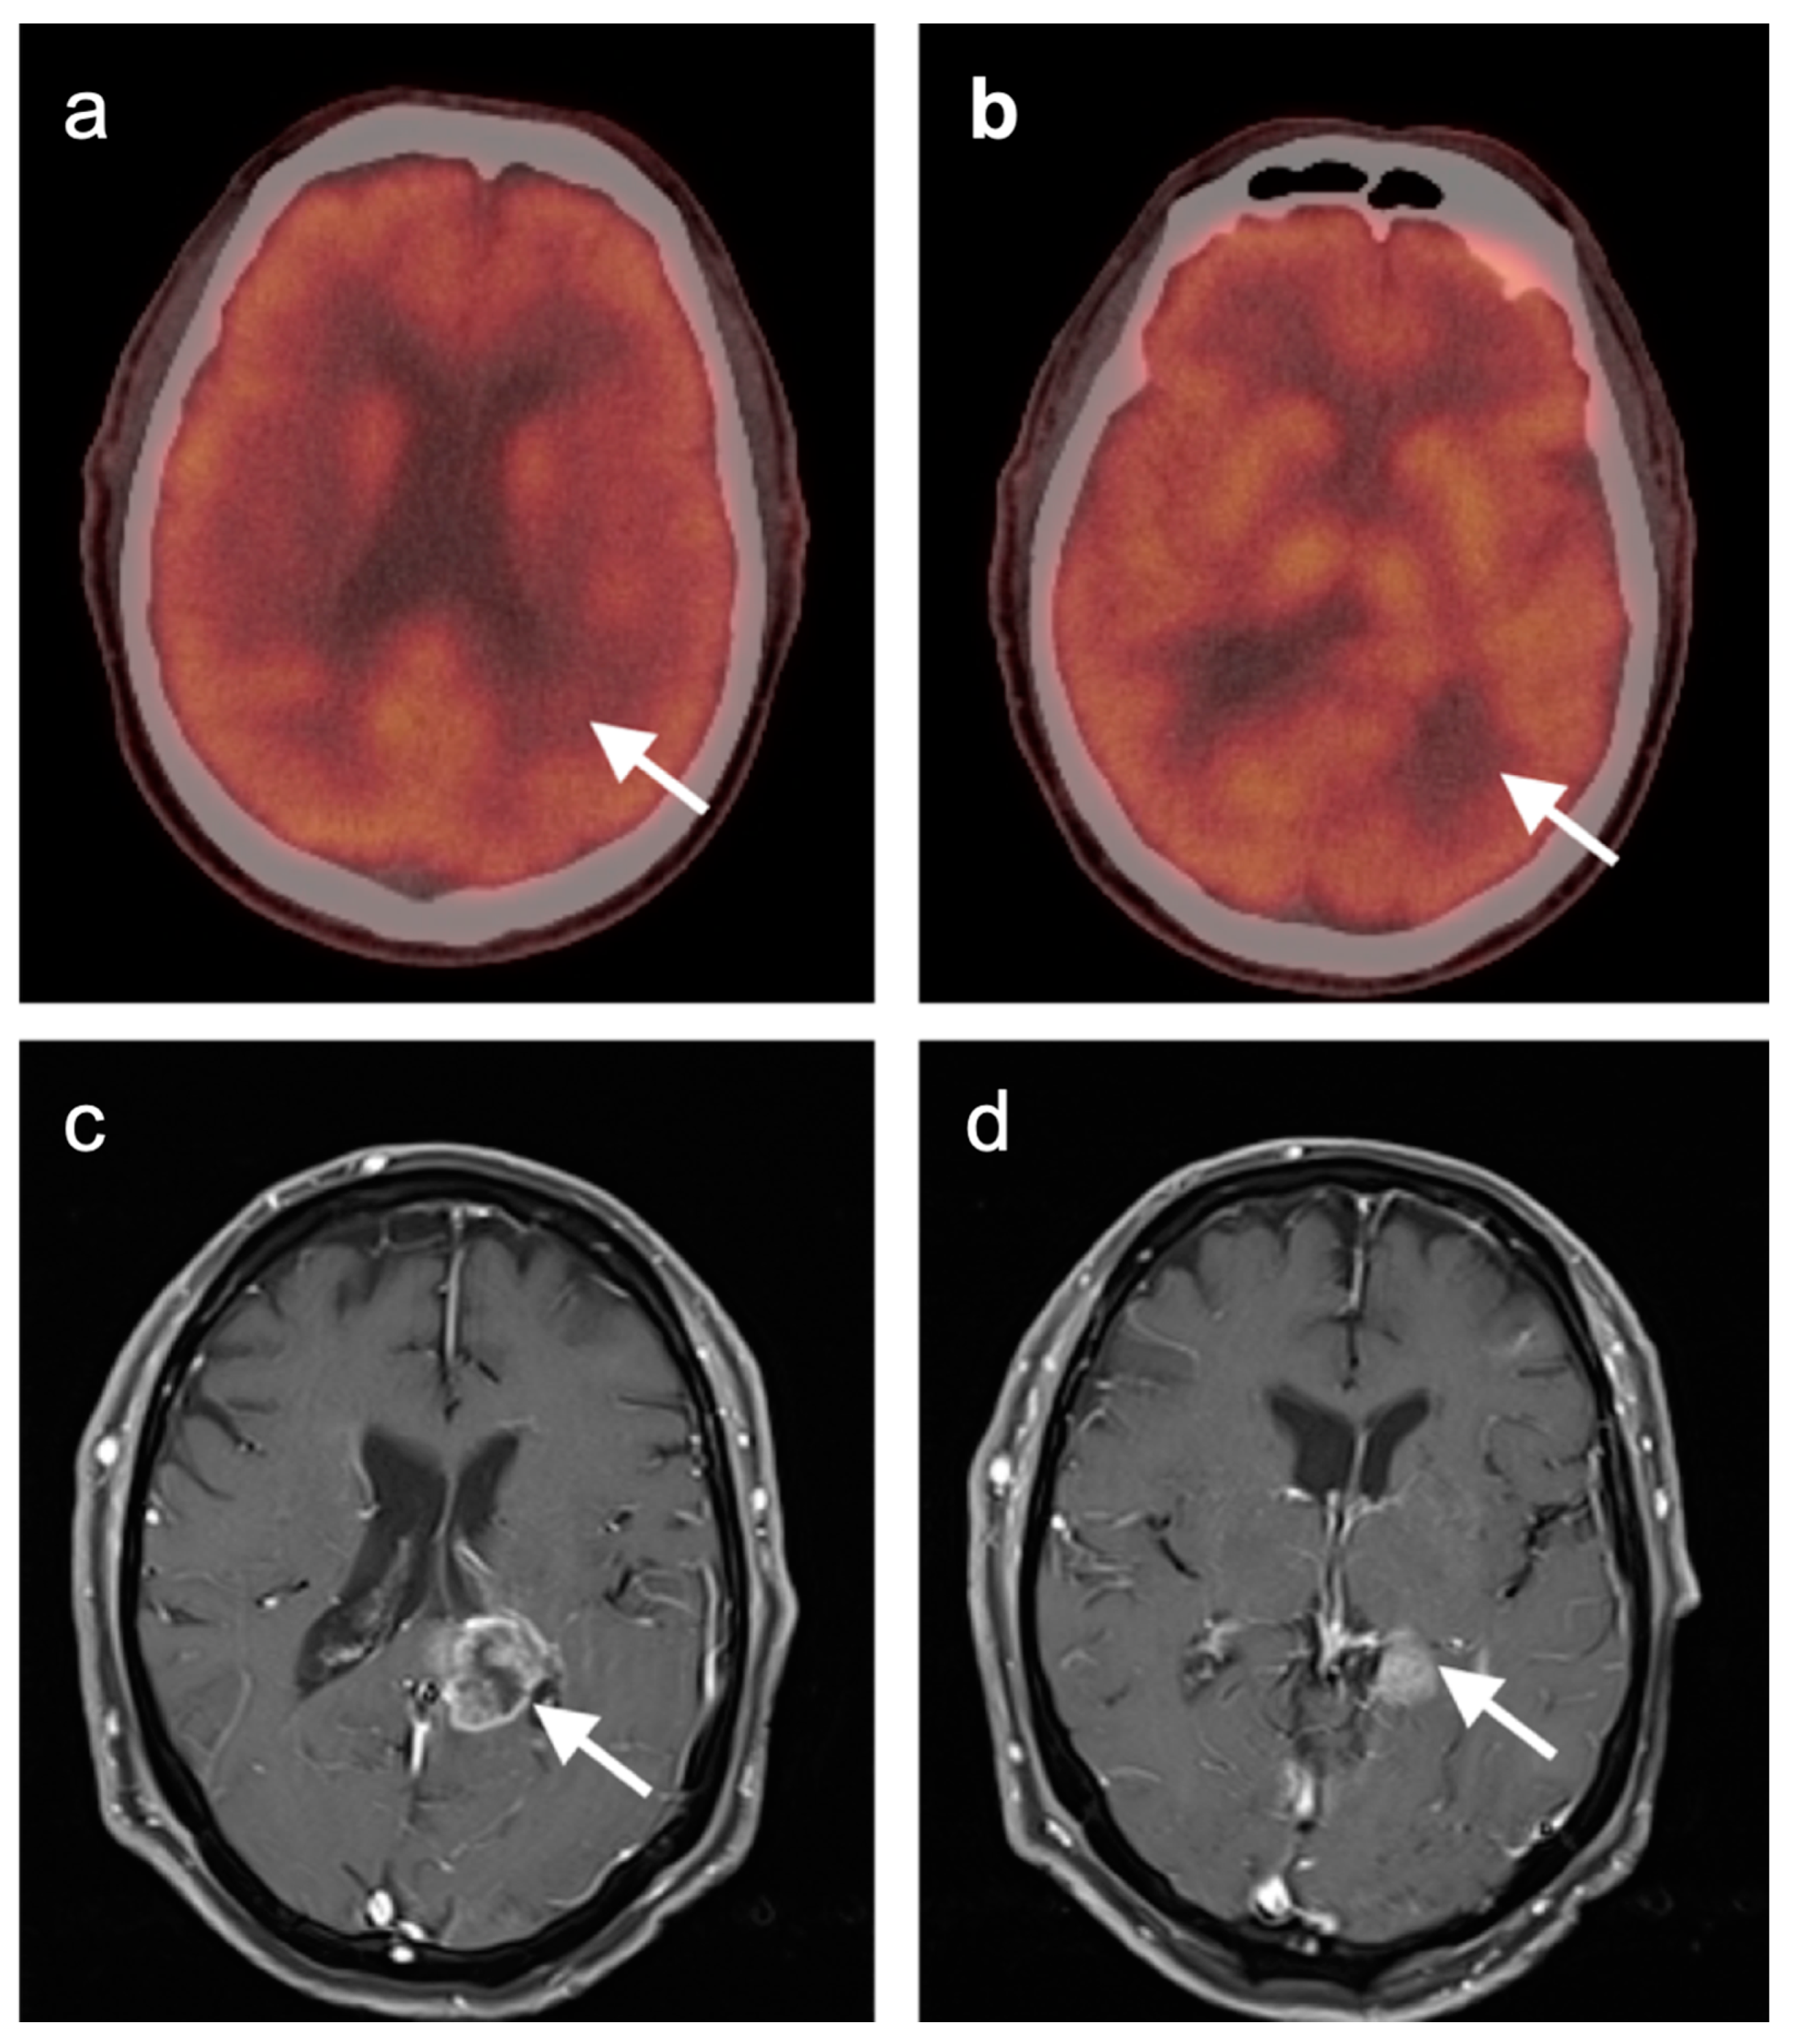

3.6. Response to Therapy

- Chao, S.T.; Suh, J.H.; Raja, S.; Lee, S.-Y.; Barnett, G. The sensitivity and specificity of FDG PET in distinguishing recurrent brain tumor from radionecrosis in patients treated with stereotactic radiosurgery. Int. J. Cancer 2001, 96, 191–197. [Google Scholar] [CrossRef]

- Horky, L.L.; Hsiao, E.M.; Weiss, S.E.; Drappatz, J.; Gerbaudo, V.H. Dual phase FDG-PET imaging of brain metastases provides superior assessment of recurrence versus post-treatment necrosis. J. Neurooncol. 2011, 103, 137–146. [Google Scholar] [CrossRef]